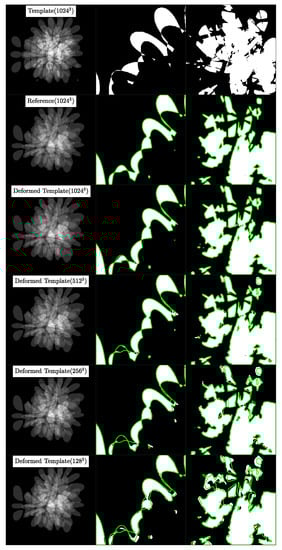

5.3. Experiment 2A: High Resolution Synthetic Data Registration

5.3.1. Dataset

5.3.2. Procedure

- We register the template image to the reference image at the base resolution n to get the velocity field . We transport using the velocity to get the deformed template image by solving Equation (3). Then, we compute the Dice score between and , which are discrete labels for and , respectively, using Equation (13).

- We downsample and using nearest neighbor interpolation to half the base resolution (for example, . Notice that we treat as a tuple. When we say , we mean ) and register the downsampled images to get the velocity . We upsample to the base resolution n using spectral prolongation and call it . We transport using by solving Equation (3) to get the deformed template image and then compute the Dice score for this new deformed template image.

- We repeat the procedure in step 2 for resolutions and and compute the corresponding Dice scores.

5.3.3. Results

5.3.4. Observations